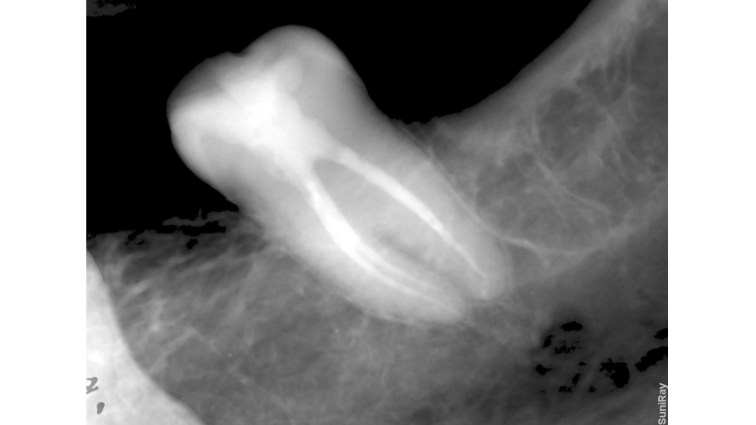

This is a “garden variety” endo. The best time to refer a case to an endodontist with a microscope is before the pulp has been touched. That way, the endodontist can control how much of tooth structure is removed to complete the endo. In this case, I had to chase all the cracks before restoring